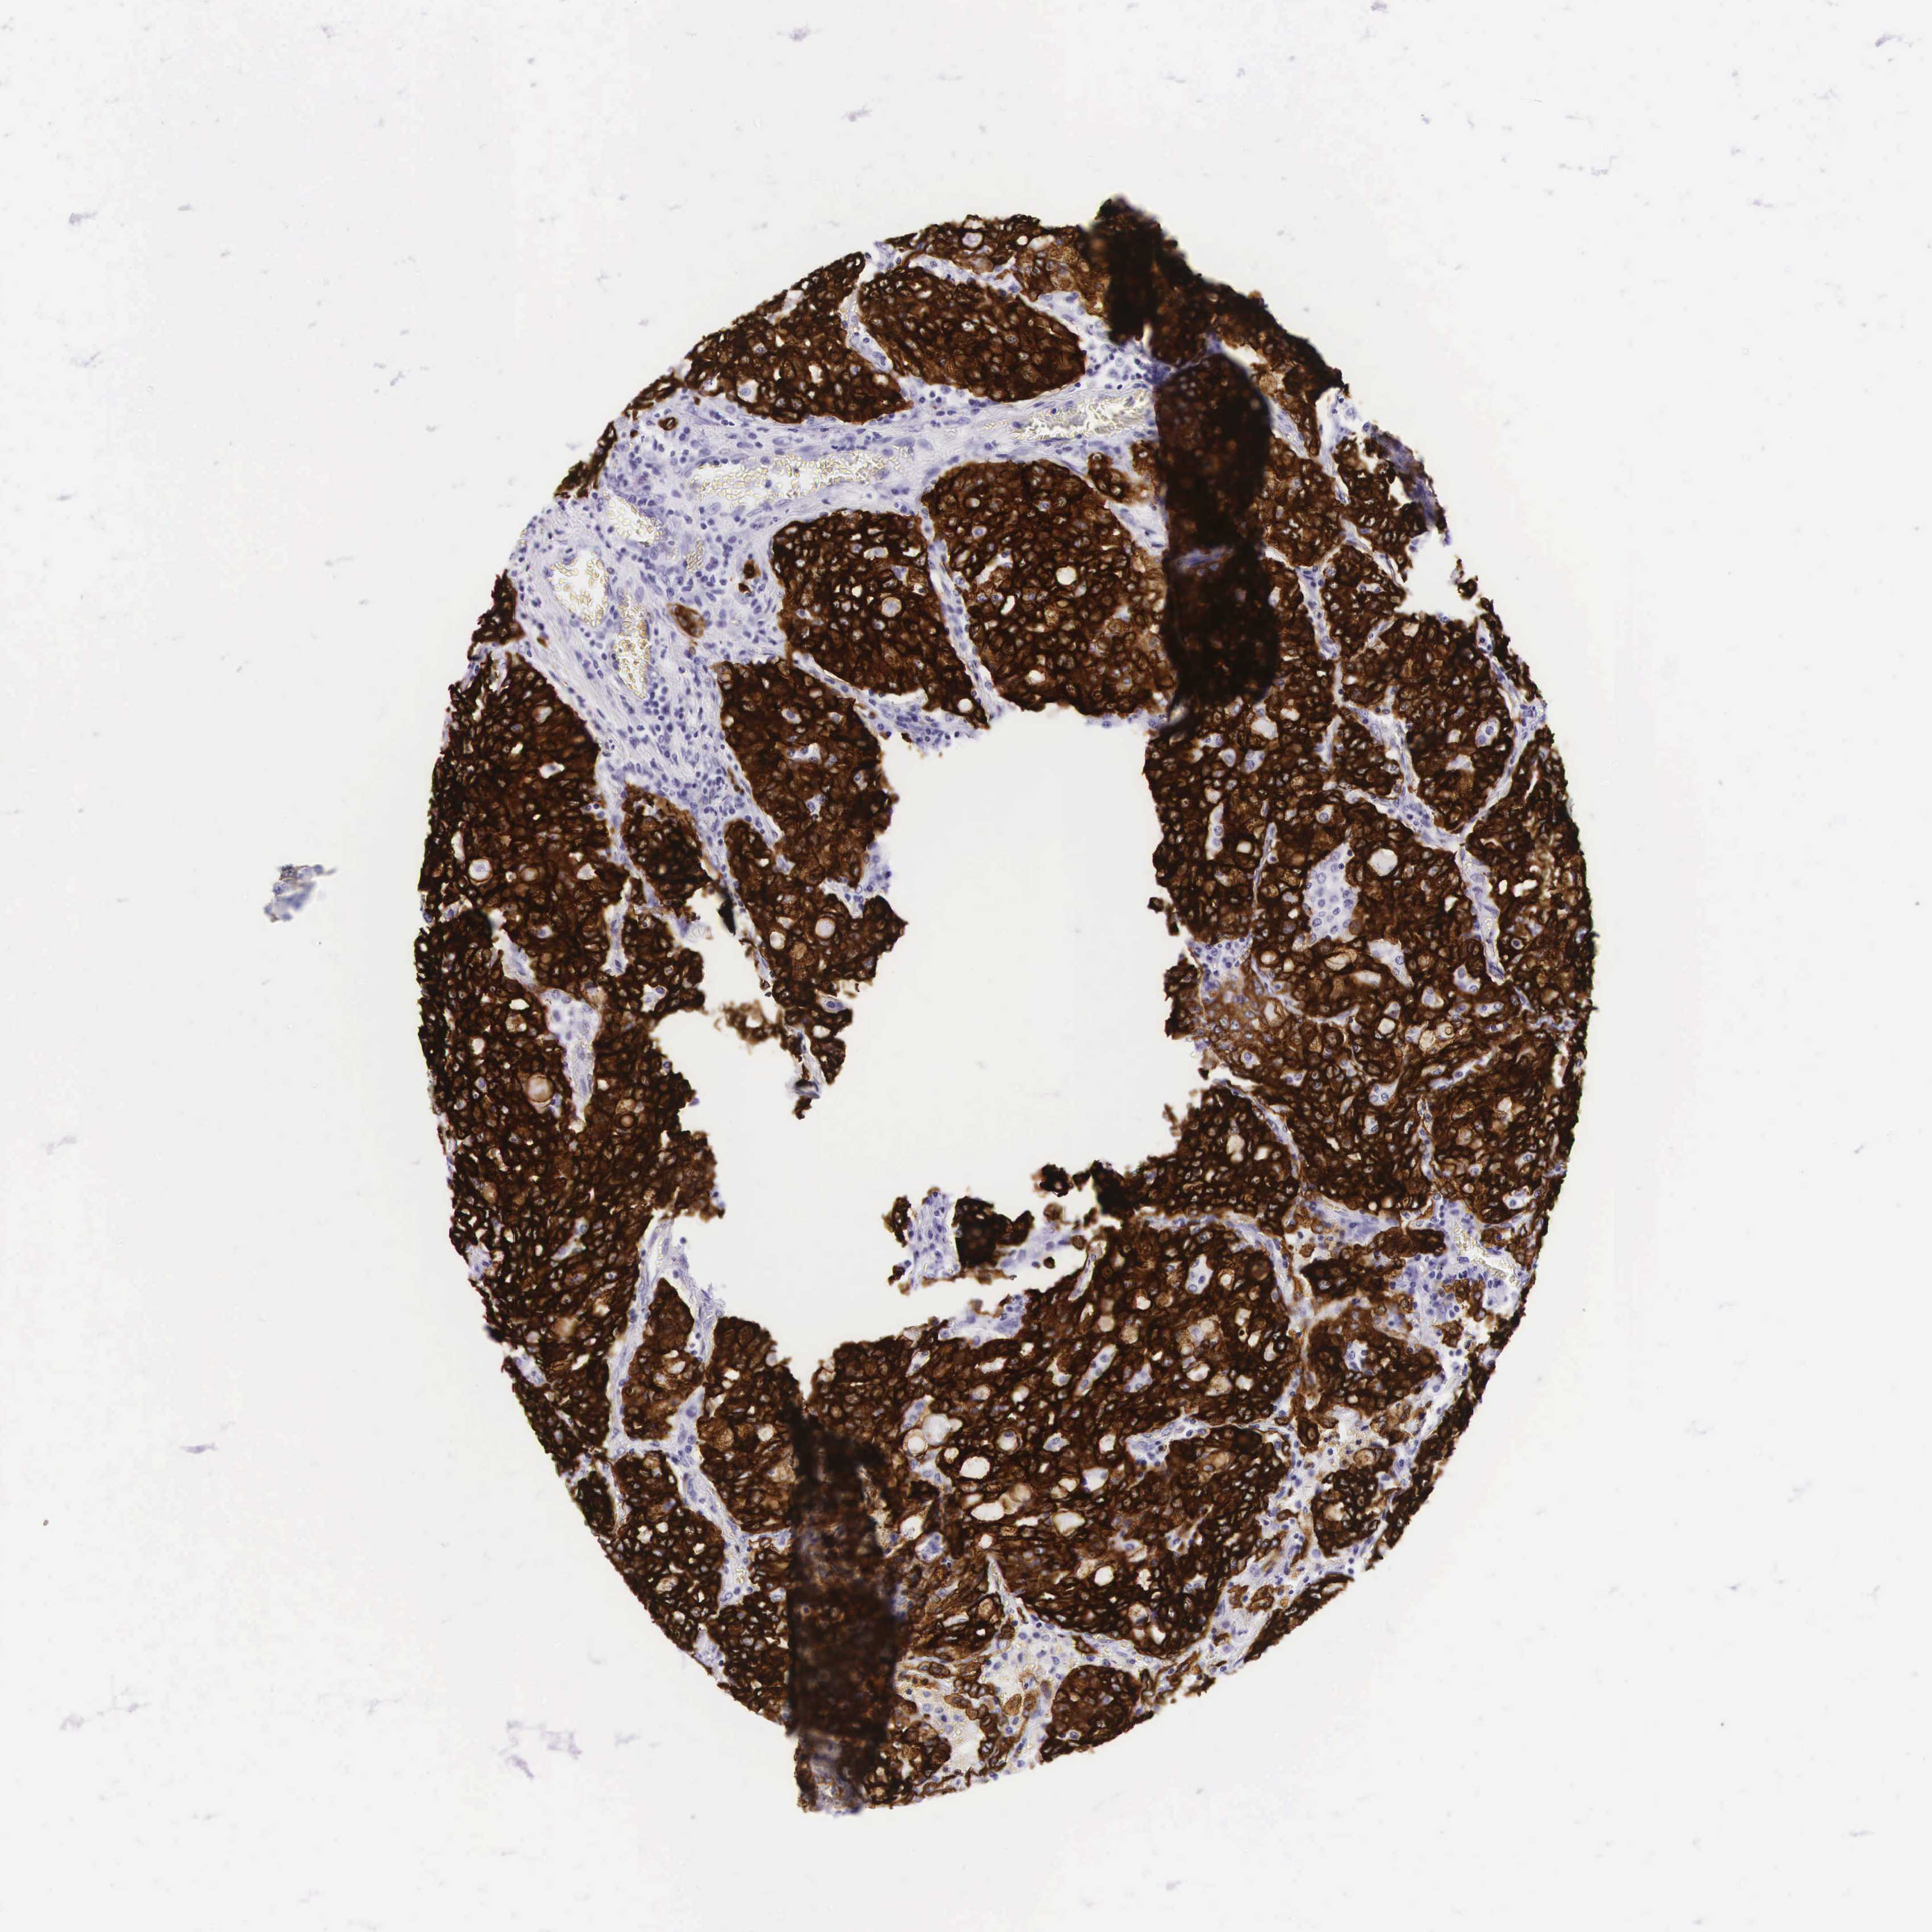

CANCER LUNG CANCER Show tissue menu

KRT18 is potential prognostic, high expression is unfavorable in Lung Adenocarcinoma (TCGA)